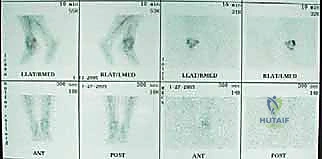

التشخيص الدقيق: حجر الأساس لنجاح العملية

يؤمن الأستاذ الدكتور محمد هطيف بأن التشخيص الدقيق يمثل 70% من نجاح جراحة مراجعة الكاحل. لا يمكن اتخاذ قرار جراحي بناءً على التخمين. تتضمن خطة التشخيص الشاملة في عيادته بصنعاء ما يلي:

- الأشعة السينية مع تحميل الوزن (Weight-bearing X-rays): لتقييم الزوايا الميكانيكية وتحديد مدى هبوط المفصل أو وجود كسور في الكعب.

- التصوير المقطعي المحوسب (CT Scan): وهو الأداة الذهبية لتقييم "المخزون العظمي" (Bone Stock). يوضح بدقة حجم الأكياس العظمية ومقدار العظم المفقود الذي سيحتاج لترقيع.

- التصوير بالرنين المغناطيسي (MRI): يُستخدم أحياناً لتقييم الأوتار والأربطة المحيطة.

- التحاليل المخبرية وسحب السوائل (Aspiration): لاستبعاد وجود أي عدوى بكتيرية خفية (مثل تحليل CRP و ESR).